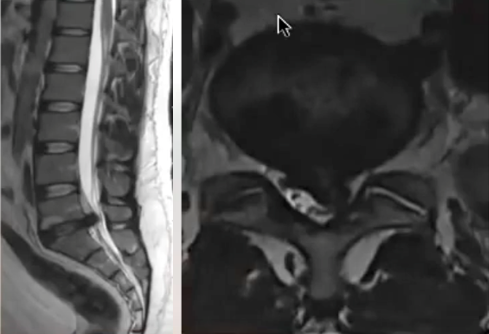

- Patients with slipped discs

- Those with spinal stenosis

- Patients with nerve compression